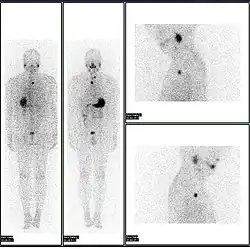

- 2D: Сцинтиграфия (от лат. «знать») — это использование внутренних радионуклидов для создания двухмерных изображений.

Сканирование костей всего тела с помощью ядерной медицины. Сканирование костей всего тела в ядерной медицине обычно используется для оценки различных патологий, связанных с костями, таких как боли в костях, стрессовые переломы, доброкачественные поражения костей, инфекции костей или распространение рака на кость.